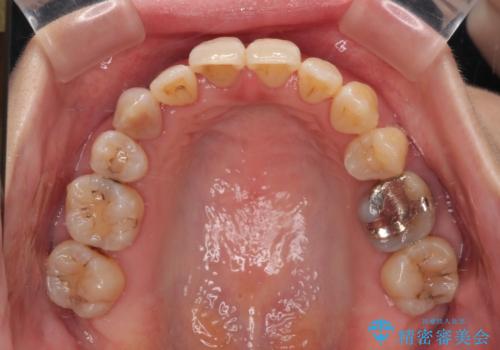

急速拡大装置 狭い骨幅を拡大した上で、顕著なデコボコを改善する抜歯矯正治療

上顎骨よりも下顎骨の幅が広く、更には下顎骨が左側に変位していたため、より良い咬み合わせを達成することを目的として、急速拡大装置を用いて上顎骨を拡大することとしました。

デコボコが強い上に、口元の突出感も気にしていたため、上下左右の小臼歯4本を抜歯して、ワイヤー装置にて矯正治療を行うこととしました。